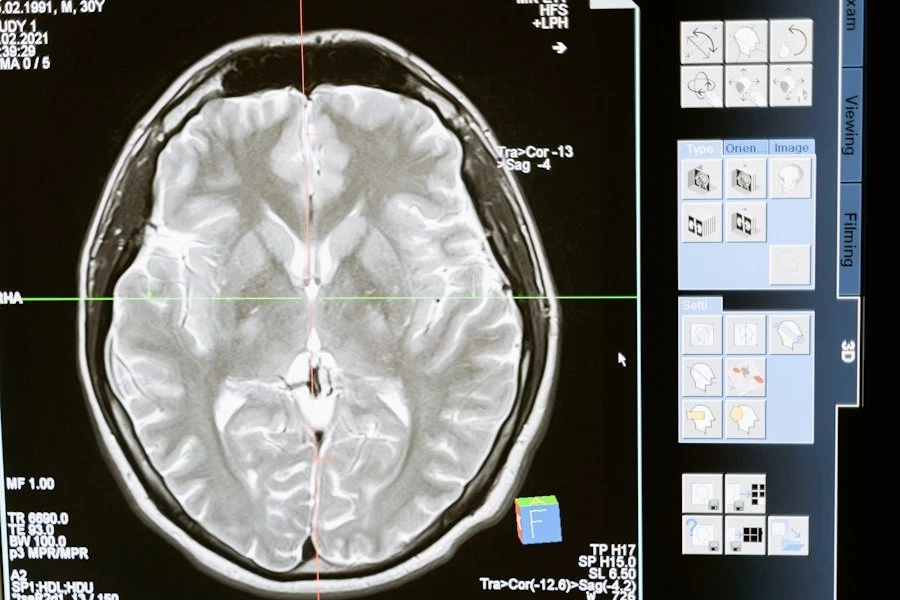

Их работа сфокусировалась на использовании двух- и трехмерных моделей компьютерного зрения, основанных на анализе данных магнитно-резонансной томографии (МРТ) мозга, как с использованием контрастного вещества, так и без него.